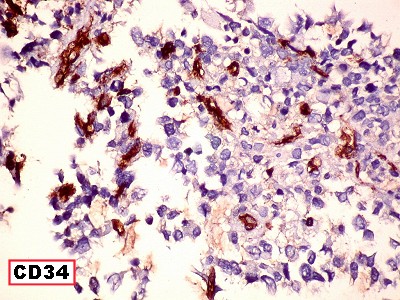

| CD34.

Positivo nos vasos, negativo no tumor |

Ki67.

Marca cerca de 90% dos núcleos neoplásicos, indicando altíssimo

índice proliferativo. |

p53.

Marca a totalidade dos núcleos neoplásicos, sugerindo mutação

do gene P53, que regula apoptose. |